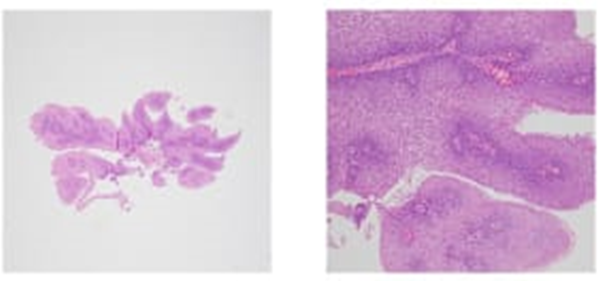

Рис.1E. Шаг 5. Оценка результатов гистологического исследования.

Fig. 1E. Evaluation of the results of histological examination.

Гистологическое заключение: плоскоклеточная папиллома с лимфоплазмоцитарной инфильтрацией.

Цитологическое заключение: группы клеток многослойного плоскоклеточного неороговевающего эпителия.

Более детальная оценка в зоне проведения полипэктомии подтверждает отсутствие рецидива.